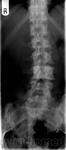

Флюороз, то конечно хорошо, но в авторском случае один позвонок "бластный"...

3.fluorosis.jpg

3.fluorosis.jpg14.7 кб

4.fluorosis.jpg

4.fluorosis.jpg14.13 кб